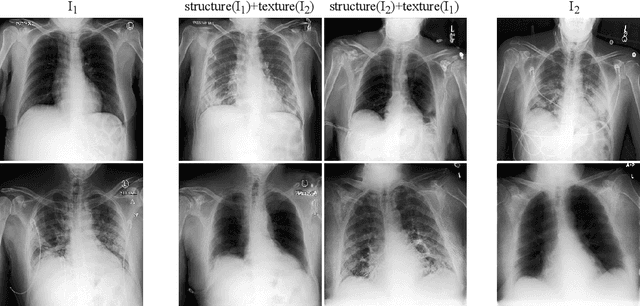

Well-labeled datasets of chest radiographs (CXRs) are difficult to acquire due to the high cost of annotation. Thus, it is desirable to learn a robust and transferable representation in an unsupervised manner to benefit tasks that lack labeled data. Unlike natural images, medical images have their own domain prior; e.g., we observe that many pulmonary diseases, such as the COVID-19, manifest as changes in the lung tissue texture rather than the anatomical structure. Therefore, we hypothesize that studying only the texture without the influence of structure variations would be advantageous for downstream prognostic and predictive modeling tasks. In this paper, we propose a generative framework, the Lung Swapping Autoencoder (LSAE), that learns factorized representations of a CXR to disentangle the texture factor from the structure factor. Specifically, by adversarial training, the LSAE is optimized to generate a hybrid image that preserves the lung shape in one image but inherits the lung texture of another. To demonstrate the effectiveness of the disentangled texture representation, we evaluate the texture encoder $Enc^t$ in LSAE on ChestX-ray14 (N=112,120), and our own multi-institutional COVID-19 outcome prediction dataset, COVOC (N=340 (Subset-1) + 53 (Subset-2)). On both datasets, we reach or surpass the state-of-the-art by finetuning $Enc^t$ in LSAE that is 77% smaller than a baseline Inception v3. Additionally, in semi-and-self supervised settings with a similar model budget, $Enc^t$ in LSAE is also competitive with the state-of-the-art MoCo. By "re-mixing" the texture and shape factors, we generate meaningful hybrid images that can augment the training set. This data augmentation method can further improve COVOC prediction performance. The improvement is consistent even when we directly evaluate the Subset-1 trained model on Subset-2 without any fine-tuning.